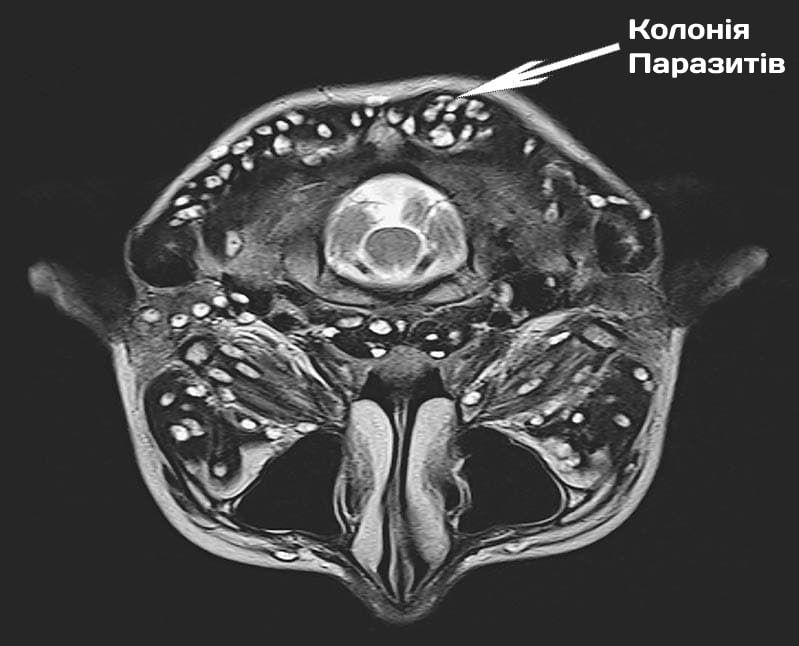

Поряд із ними існують тисячі паразитів, які можуть жити у вашій печінці, мозку, легенях, крові, шлунку. І практично всі вони є смертельними. Частина відразу починає діяти агресивно і руйнує організм. Частина – до певного часу діє непомітно, поки їх кількість не стане такою, що організм-носій вже не може витримувати і людина вмирає. Вони провокують масу смертельних ускладнень: інфаркти, ракові пухлини, цироз печінки, нефрит, розкладання нирок та сотні інших, більш рідкісних, але не менш смертельних.

3. Ехінококові кісти серця. Зараження пацієнта ехінококами було виявлено надто пізно. Лікуючий лікар вважав, що в нього просто ішемічна хвороба серця і стенокардія, але правда виявилася значно більшою. жорстокий. Оперувати було вже марно, а консерватине лікування не дало плодів. Замінити серце теж не вийшло - не було донорів. У результаті пацієнт помер не приходячи до тями.